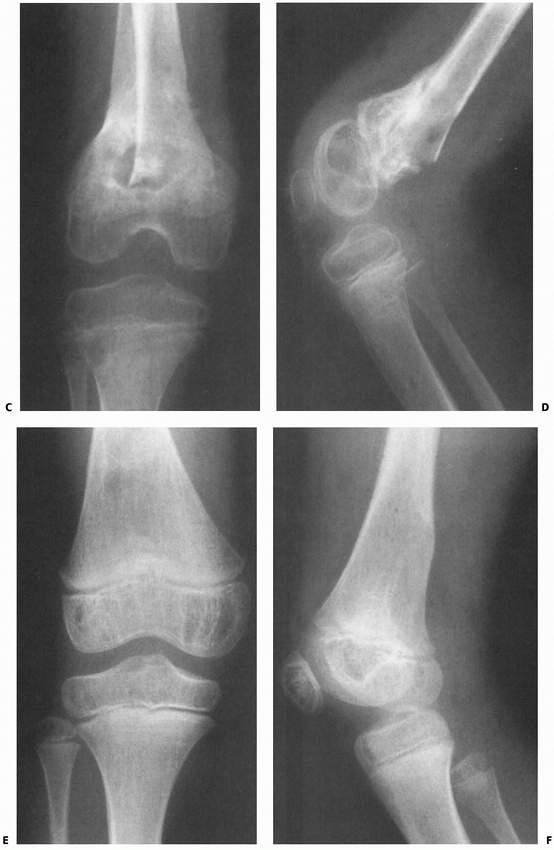

![]() |

FIGURE 23-5 (continued)

The fracture was irreducible by closed methods and required open reduction, internal fixation, and repair of a popliteal artery laceration. C,D. Incomplete reduction Salter-Harris type II fracture in a 6-year-old girl with 25 degrees of posterior angulation and abundant callus formation. E,F. Four years later, remodeling has occurred and no growth disturbance is noted. Results such as this cannot be relied upon, and early anatomic reduction is recommended. |